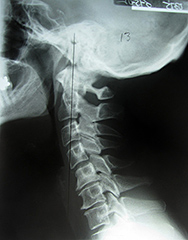

Fig. 4: Lateral Cervical (Abnormal)

Figure 3 represents a normal cervical spine as seen from the lateral view. The lordotic curve provides shock absorption, the disc spaces appear to be full and the cervical gravity line, which is located by a point on the anterior third of the odontoid process then drawing a plumb line straight down, represents the center of gravity of the weight of the head (approximately 10% of body weight). In the optimal state, all bones in the neck should share in the distribution of this weight. In Figure 4, the head is grossly anterior to all of the bones in the cervical spine, the spine is straight and the loading of this neck is highly abnormal.